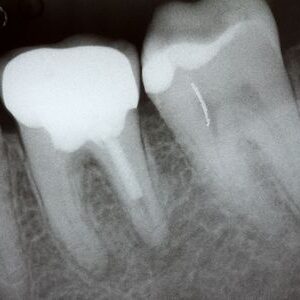

Endodontists use materials and equipment designed to make your treatment both effective and comfortable. State-of-the-art tools such as digital x-rays and 3D cone beam CT imaging make diagnosis and treatment planning more efficient.According to the American Association of Endodontics (AAE), the space inside a root canal is smaller than FDR’s ear on a dime. Without specialized equipment, it is easy to miss affected areas during a root canal treatment, causing recurring infection. Endodontists use operating microscopes to view the tiny spaces within the root canals for thorough treatment with lasting benefits.